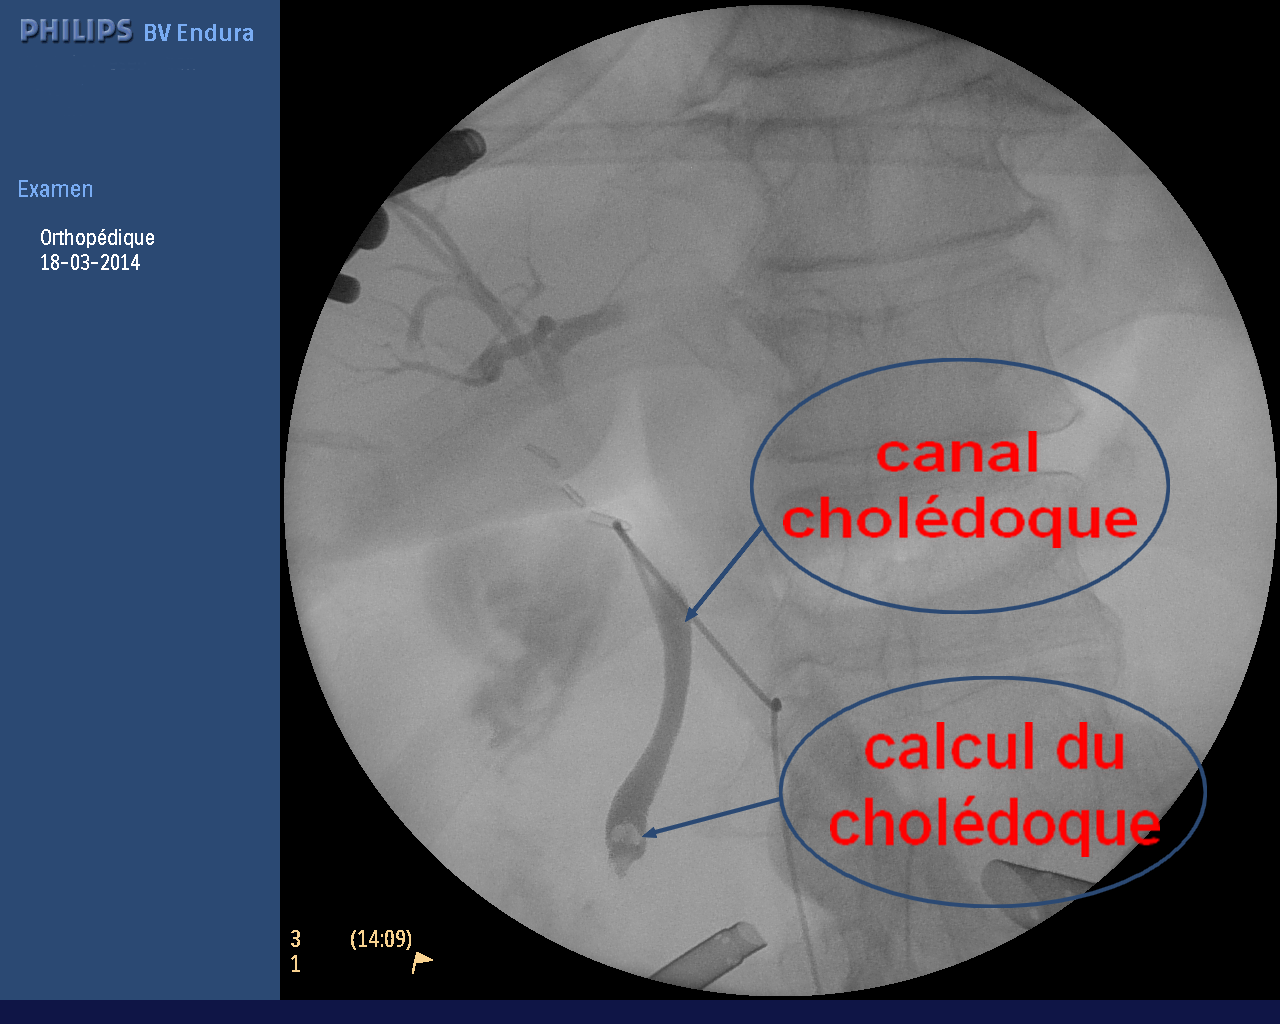

Tout savoir sur l'ablation de la vésicule biliaire. L'ablation de la vésicule biliaire, également appelée cholécystectomie est une intervention chirurgicale régulièrement pratiquée qui vise à retirer la vésicule biliaire. Cet organe en forme de poire situé sur le côté droit de l'abdomen, juste sous le foie va servir à.. avoir la diarrhée après une cholécystectomie ou une ablation de la vésicule biliaire, Maintenant quoi?